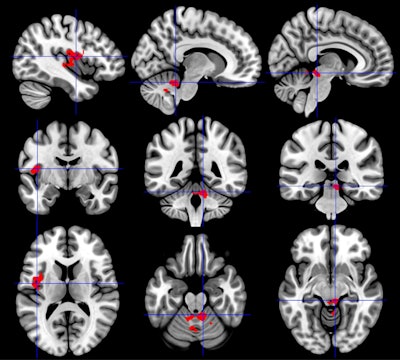

The insula region of the brain (right column) has greater activation in individuals with chronic fatigue syndrome than in healthy controls or those with Gulf War illness. By comparison, the cerebellum (middle column) has less activation in Gulf War illness than healthy controls or those with chronic fatigue syndrome. In addition, the brainstem showed less activation (left column) in Gulf War illness and greater activation in chronic fatigue syndrome. All the differences were observed after exercise. Images courtesy of Stuart Washington, PhD.In the second study, the researchers compared brain region activation based on blood oxygenation level dependent (BOLD) contrast among 79 veterans with Gulf War illness, 36 people with chronic fatigue syndrome, and 31 healthy controls. The goal was to explore nine brainstem regions of interest and four media structures, all of which are linked to memory performance, to illustrate the degree to which these conditions have differing effects.

Again, all subjects underwent 3-tesla fMRI scans before and after two exercise stress tests. Cognitive evaluations were done through 2-back working memory tasks. The researchers targeted nine brainstem regions of interest and four media structures, all of which are linked to the ability to determine threats, arousal, modulation of chronic pain, sleep, and other neurobehavioral functions.

Before exercise, fMRI showed significantly decreased BOLD activity among chronic fatigue syndrome subjects compared with healthy controls in the pedunculopontine nucleus, which is associated with learning, reward, and voluntary arm and leg movement. All other brainstem regions showed no significant difference in activity among the three groups. After exercise, Gulf War illness patients had significantly reduced BOLD activity compared with chronic fatigue syndrome subjects in eight brain regions, while no significant difference was found in healthy controls.